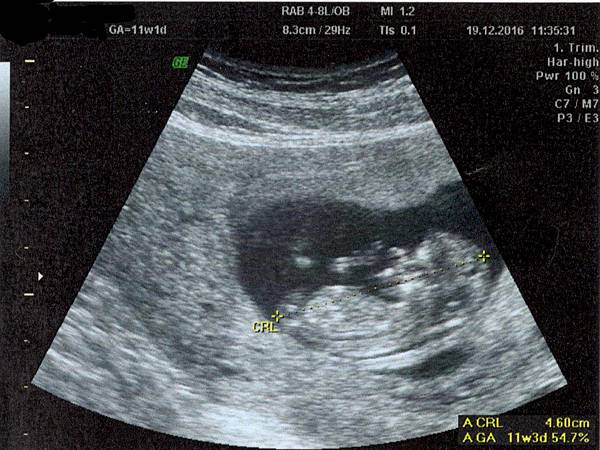

第11周產檢:T21抽血‧唐氏綜合症檢查(超音波度胎兒頸皮)

上一次做產檢是兩個星期前,是孕期第9周第1天,兩個寶寶的CRL分別是2.48cm和2.25cm。而正是在踏入第9周後我的孕初期不適達到了巔峰,食欲不振,每天都覺得很不舒服。過去兩個星期,我常去麥當奴吃「開心樂園餐」,點一個「芝士漢堡包」、「細橙汁」和「細薯條」,因為只有這個餐,份量少且因為比較「乾身」,所以在吃的時候可以吸收口腔裏不斷湧出來的酸苦胃酸,讓我能感受到食物的美味。但通常在用餐後的五分鐘內,口腔裏又會滿佈苦澀的滋味,完全感覺不出自己之前吃過什麼好吃的東西。